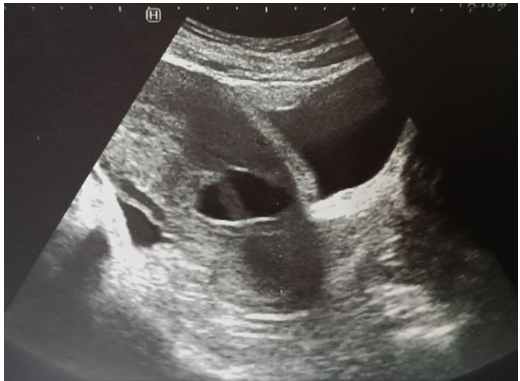

Pelvic ultrasound (figure 3): isthmic pregnancy on uterine scar

Biological workup: BHCG: 15mUI/mL vs 37,184 mUI/mL on 05/09/2024

Figure 3: Isthmic Pregnancy on Uterine Scarring